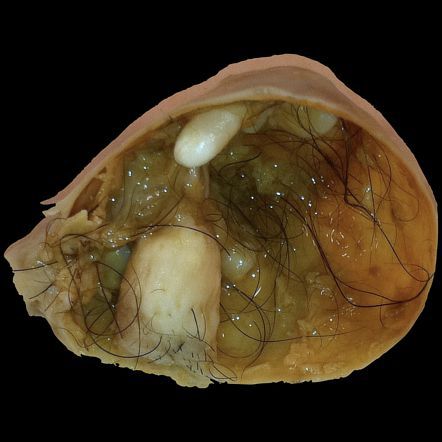

Mature cystic ovarian cyst is also known as ovarian dermoid cyst. Multiple germ cell layers give rise to this neoplasm. It is the most common ovarian neoplasm in young women. Mature cystic ovarian cysts are found incidentally due to their asymptomatic nature. However, these cysts can cause ovarian torsion resulting in severe pelvic pain. Plain radiography indicates structures with calcium element. Ultrasonography is the modality of choice for diagnosis; it demonstrates cystic adnexal mass. Reference: https://radiopaedia.org/articles/mature-cystic-ovarian-teratoma-1

These cysts are Dermoid cyst &occur in young ladies &besides pain if they enlarge& be bilateral may cause infertility also.